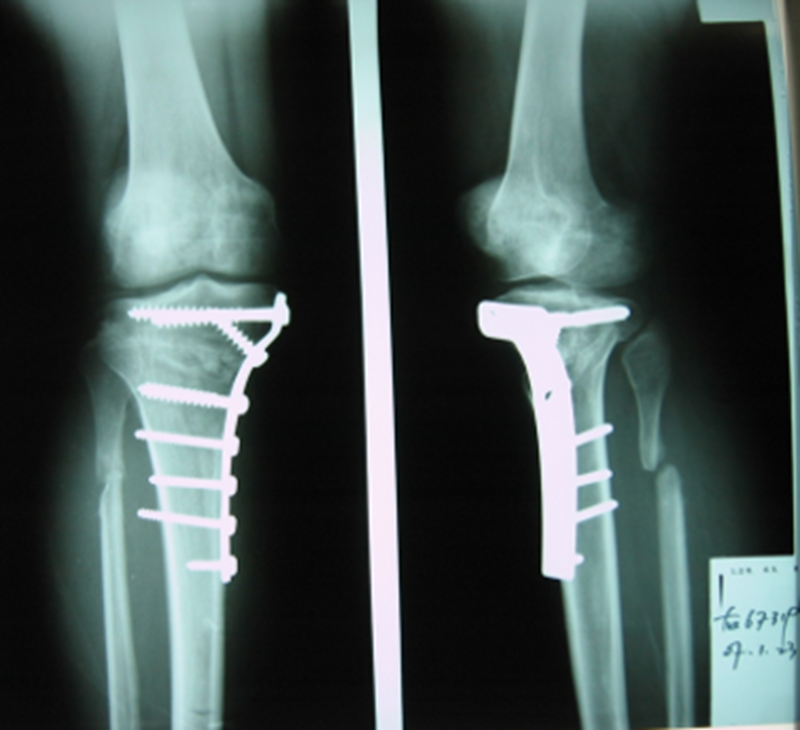

术后6月X片示右膝内翻、前倾畸形已矫正,胫骨截骨处愈合,腓骨未愈合,但无症状。